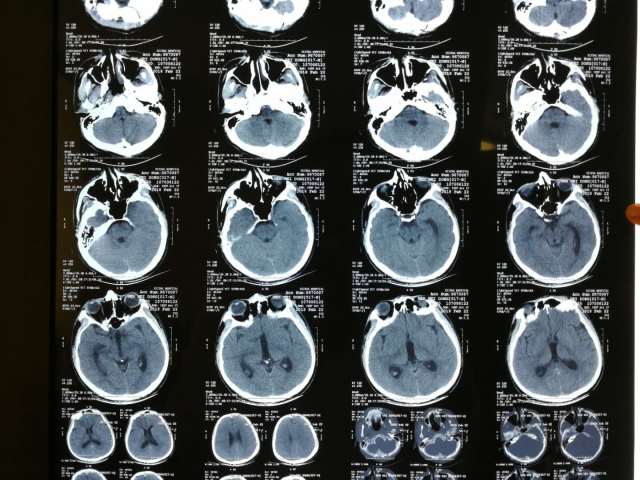

颅脑ct解剖(图文)skc影像园xctmr.